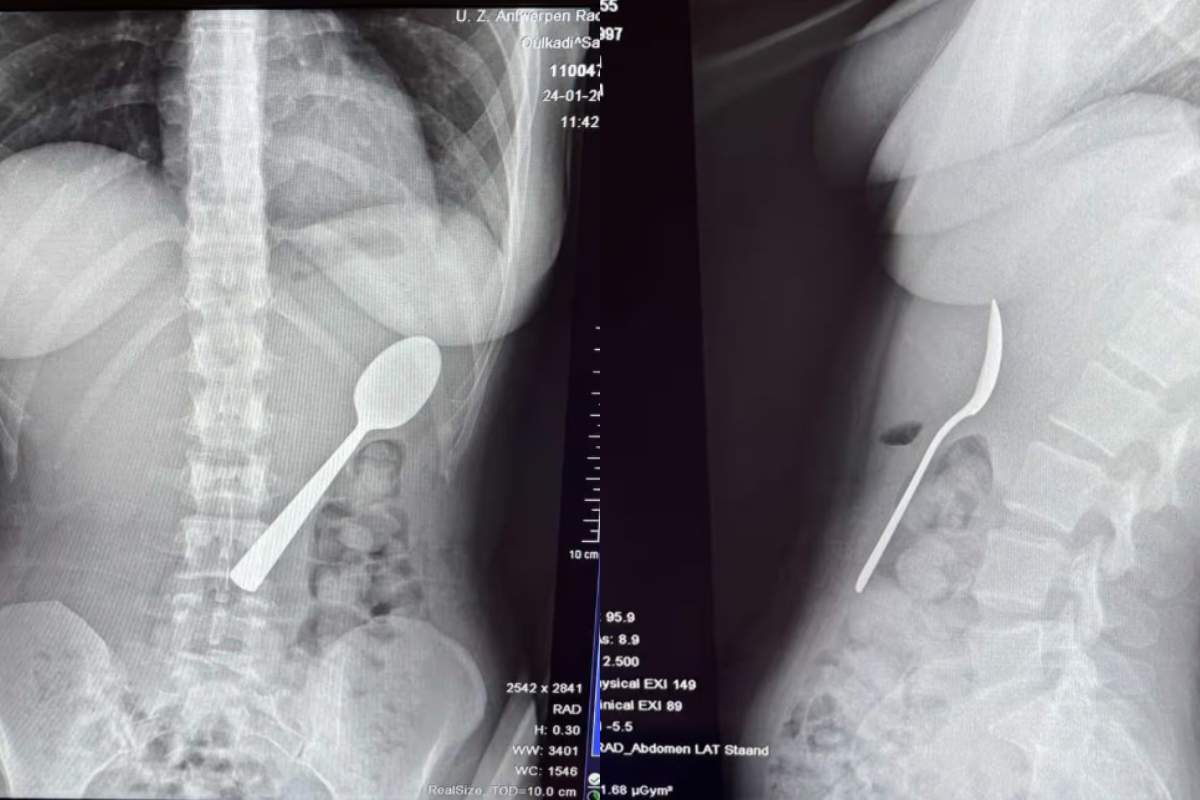

O femeie a înghițit o lingură de 17 cm în timp ce mânca iaurt. Cum a fost posibil | Galerie Foto | Imaginea 4 din 4

O femeie a înghițit o lingură de 17 cm în timp ce mânca iaurt